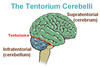

What is the difference in location of CNS tumors in adults vs. children?

Adults: supratentorial

Children: below the tentorium